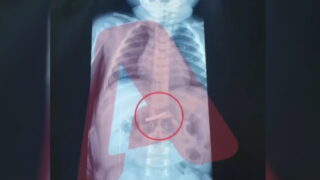

16:40 07.01.26 Μιχάλης Μητρούσης: «Όταν είδαν την εγκληματική πράξη αυτού που με χτύπησε, αναρωτιόντουσαν αν ζω» «Με έσωσε το Mega στο ατύχημά μου» παραδέχτηκε ο ίδιος